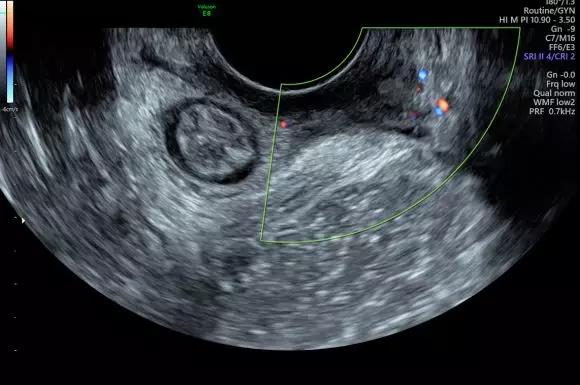

GE LOGIQ E9/S8及Voluson E8超聲儀

Voluson E8超聲儀:

廣泛應用于婦產超聲臨床領域,尤其在產科、不孕不育生殖醫(yī)學和女性盆底功能障礙性疾病等領域,提供高品質圖像及專業(yè)的婦產超聲臨床解決方案。

案例圖

女性不孕檢查

女性產后盆底功能檢查